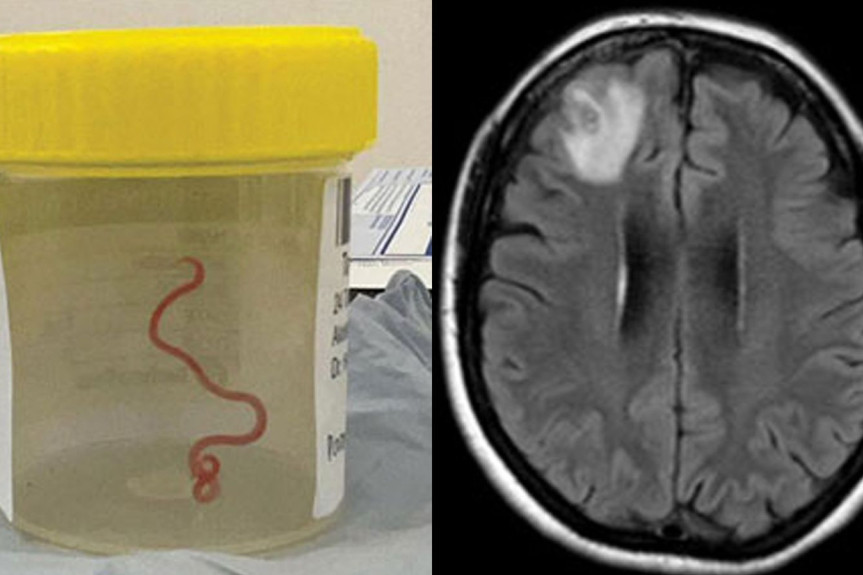

Nekoliko lekara je primetilo tamnu tačku na skeneru njegovog mozga, a zatim mu se javio i doktor koji je rekao da sumnja da se u njegovoj glavi nalazi nezvani gost.

On je verovao da je abnormalnost koja se vidi na njegovim snimcima sa skenera "prouzrokovana crvom koji je ušao u moj mozak i pojeo njegov deo, a zatim umro", rekao je Kenedi, a prenosi "Njujork tajms".

Kenedi je rekao da tokom višenedeljnog skeniranja nisu primećene nikakve promene na njegovom mozgu i da su lekari zaključili da cista koju su videli na snimku sadrži ostatke parazita. On ne zna vrstu parazita niti gde se mogao zaraziti, iako sumnja da je to moglo biti tokom putovanja kroz Južnu Aziju.

Nekoliko stručnjaka za zarazne bolesti i neurohirurga misle da je u pitanju larva svinjske pantljičare.